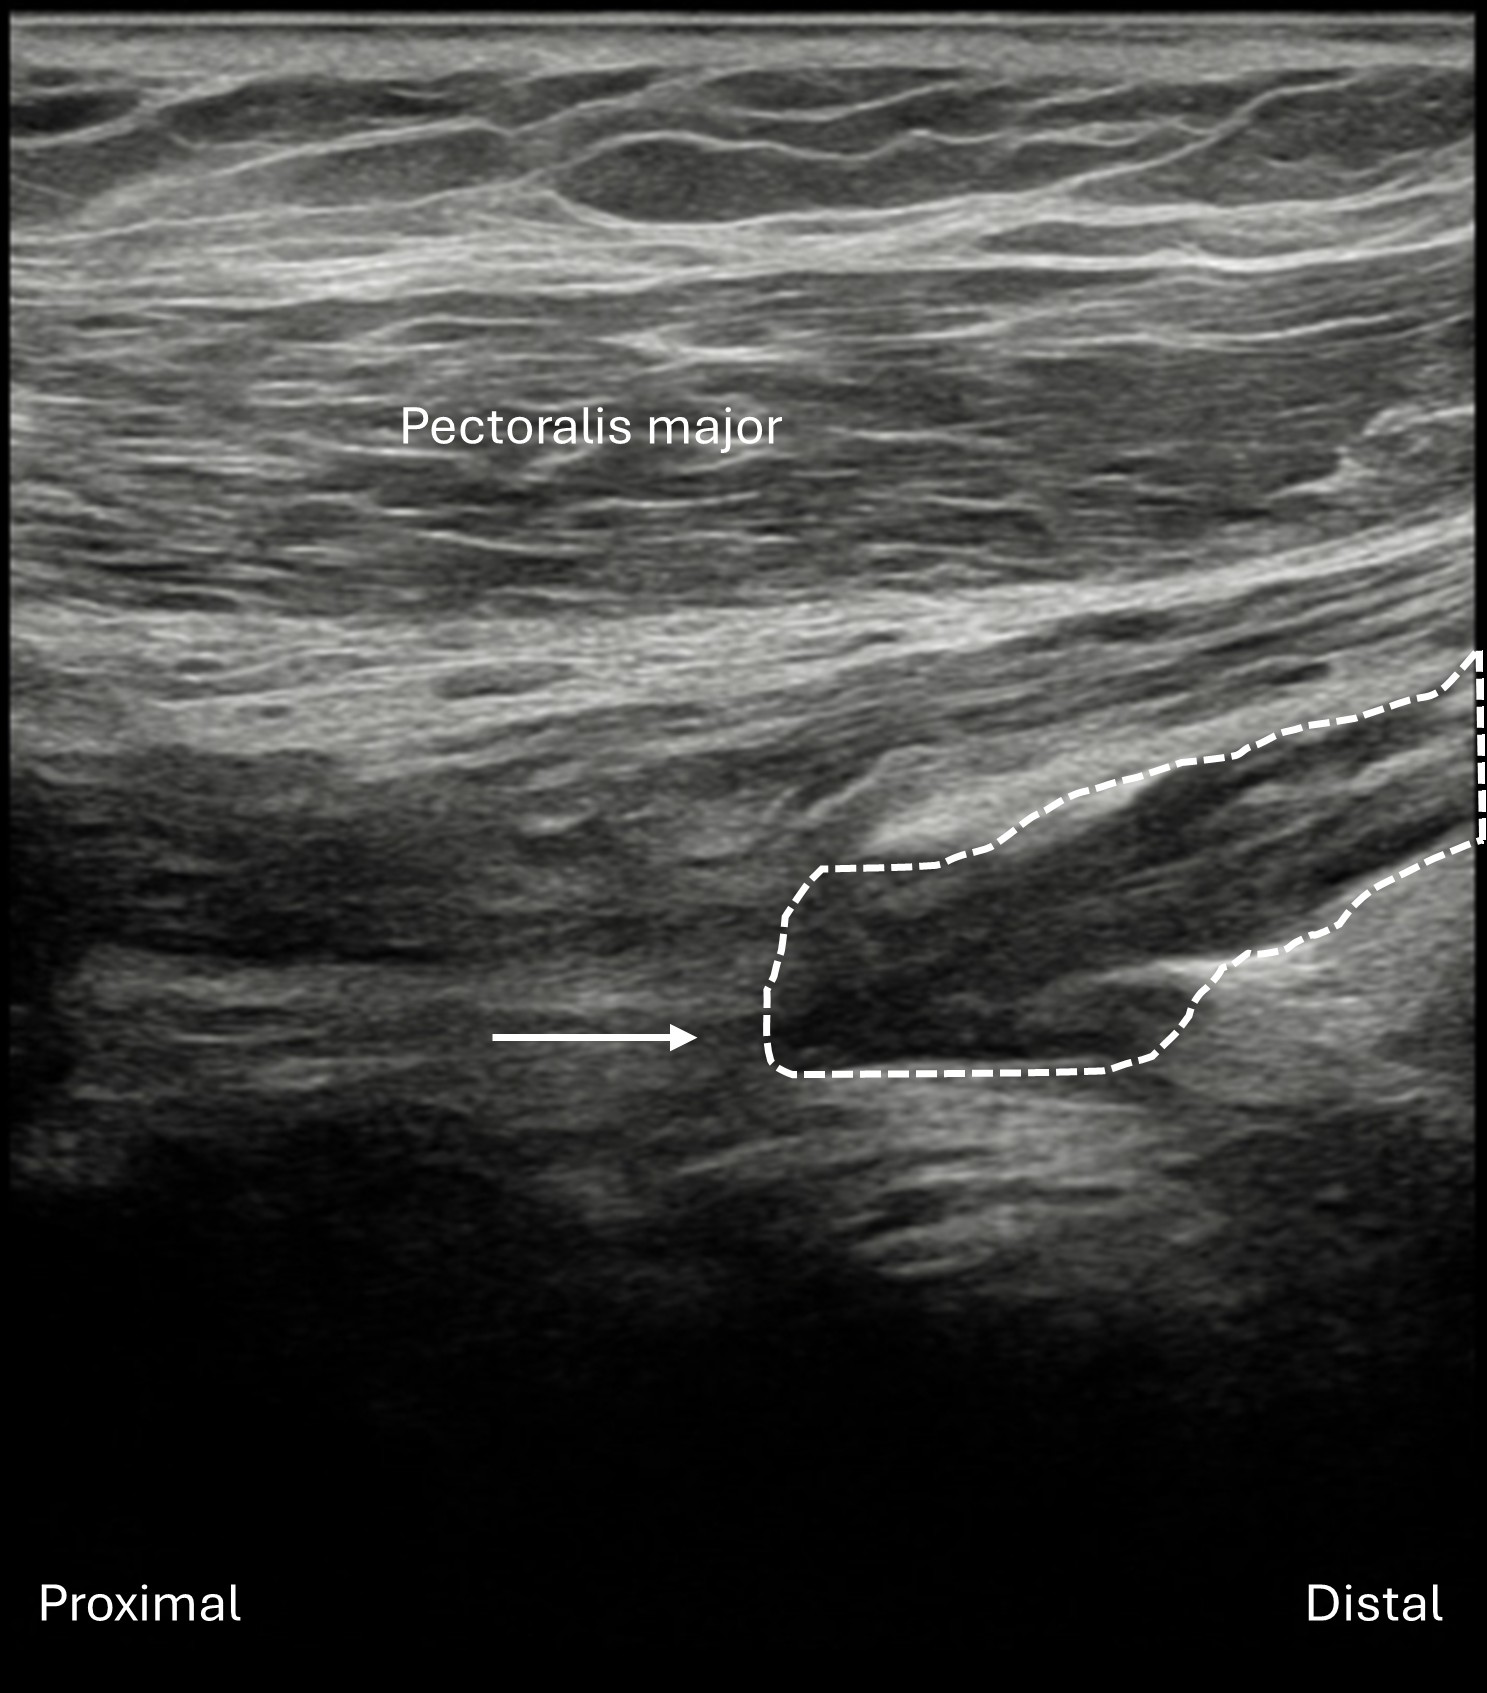

Labeled long axis view of the lateral cord of the right brachial plexus lying deep to the pectoralis major and minor muscles in the infraclavicular view. The lateral cord (dashed line) is seen to approach distal to proximal but abruptly ends (arrow) as the cord becomes focally hypoechoic and disorganized, indicating complete lateral cord transection (neural discontinuity or neurotmesis).

Unlabeled long axis view of the lateral cord of the right brachial plexus in the infraclavicular view.